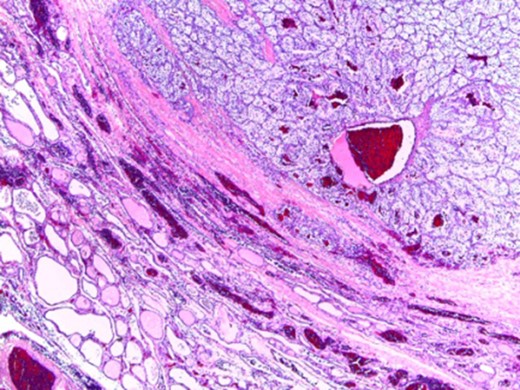

Gross examination revealed a thyroid lobe and isthmus weighing 52 g. The right lobe measured 3.8 × 5.8 × 3.5 cm3 while the isthmus measured 2.5 × 1.5 × 1 cm3. The specimen was transected revealing an intrathyroidal nodule, apparently encapsulated, yellow in color, with cystic and hemorrhagic areas measuring 4.2 × 3.5 cm2 as presented in Fig. 1.

In microscopic evaluation the tumor had a predominantly ‘clear cell’ morphology, typical of RCC as shown in Figs 2 and 3.

Normal thyroid tissue on the lower left corner; clear cells in the upper right quadrant.